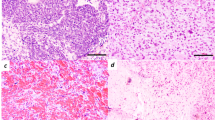

It is well known that protein expression profiles differ both between tumours with different histopathologic grades (Ware et al, 2003; Iwadate et al, 2004) and between different tumour stages (Cheung et al, 2004; Roblick et al, 2004). However, to our knowledge, the finding that the tumour protein expression profile changes over time in histologically identical tumours is novel. This may be due to molecular changes in the tumour cell biology per se, but changes in the tumour–host interaction may also contribute. In our experience, however, the BT4C cells grow homogenously in the rat brain without any obvious visible changes in the cellular distribution within the tumour, until late in the course of progression when necrosis may appear. Nevertheless, necrosis is generally not present at the time points when tissues were sampled in this study (Bergenheim et al, 1994) and radiotherapy alone has only a growth inhibitory effect without altered morphology (Johansson et al, 1999). Therefore, the observed changes in protein expression were not clearly correlated to gross morphological changes in the tumours. For this study we found it most important to account for this variation of protein expression over time in our comparative analyses. Thus, all comparisons between tumours were performed on tissues harvested at the same time point after implantation.